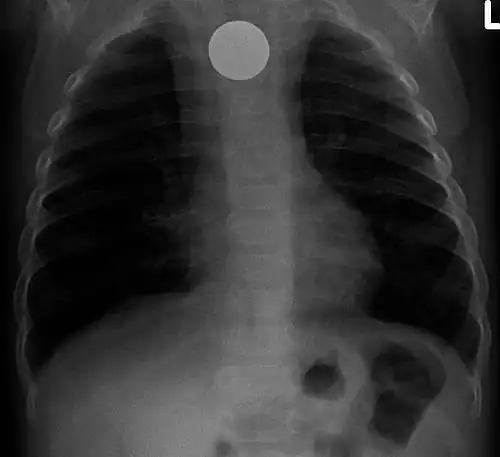

A coin seen on AP CXR in the esophagus -